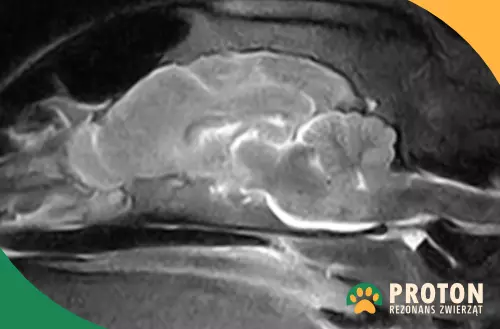

Obraz RM głowy psa

Rezonans głowy psa